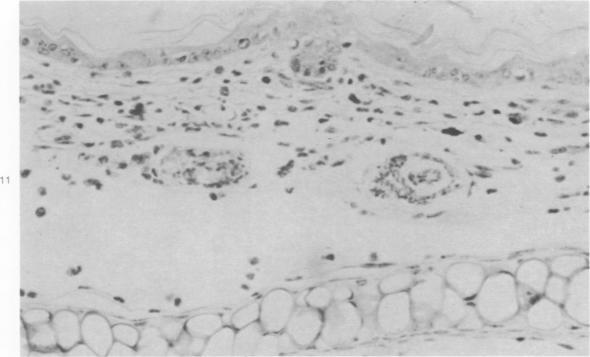

Exposure of the mouse skin to Schistosoma mansoni cercariae gives rise to acute, exudative inflammation in both normal and immune mice, but the immune response is anamnestically accelerated and is oesinophil-enriched, thereby enhancing opportunities for tegumental contact of schistosomula with host leukocytes, particularly with eosinophils. Many of the inflammatory changes occurring within the first 48 hours after exposure are due to cercarial products, e.g., "penetration tracts," but some remain demonstrable when schistosomula metamorphosed in vitro are injected intradermally and are therefore directed against the schistosomula themselves, such as the leukocyte "streaming patterns" seen in their pathways. In contrast to earlier observations in primates, cellular responses to schistosomula in the mouse lung 4 days after penetration are minimal in either normal or immune mice. Thus, immune cellular responses to schistosomula in mice are limited to an early time period after cercarial penetration and are morphologically suggestive of an antibody-mediated response rather than of delayed hypersensitivity. Our observations complement earlier evidence suggesting that antibody-mediated host leukocyte contact with schistosomula initiates the killing of challenge parasites in immune mice, with the eosinophil probably playing a crucial role.

将曼氏血吸虫尾蚴暴露于小鼠皮肤会在正常小鼠和免疫小鼠中引发急性渗出性炎症,但免疫反应会呈回忆性加速且富含嗜酸性粒细胞,从而增加了童虫与宿主白细胞(特别是嗜酸性粒细胞)体表接触的机会。暴露后最初48小时内发生的许多炎症变化是由尾蚴产物引起的,例如“侵入道”,但当在体外变态的童虫皮内注射时,一些变化仍然明显,因此是针对童虫本身的,比如在其路径中看到的白细胞“流动模式”。与早期在灵长类动物中的观察结果相反,在正常或免疫小鼠中,穿透后4天小鼠肺内对童虫的细胞反应都很轻微。因此,小鼠对童虫的免疫细胞反应仅限于尾蚴穿透后的早期阶段,并且在形态学上提示是一种抗体介导的反应而非迟发型超敏反应。我们的观察结果补充了早期证据,表明抗体介导的宿主白细胞与童虫的接触启动了免疫小鼠中对攻击寄生虫的杀伤,嗜酸性粒细胞可能起着关键作用。